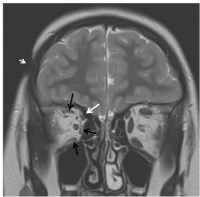

A 3-year-old girl developed a hyperchromic lesion with an ivory-like centre on the lateral aspect of her right eyebrow. The lesion subsequently extended to the temporal area, and 2 years later she presented intermittent exotropia. Cerebral computed tomography (CT) scan was normal and no treatment was advised. After 4 years she was referred to our unit and finally, at 7 years of age, a diagnosis of LiS of the face was made. On examination she presented right exotropia and hypotropia due to impairment of superior, medial and inferior rectus and superior oblique muscles. A linear violaceous lesion with moderate subcutaneous tissue loss and adnexa atrophy was present on the temporal area with small ivory-like centre. Cerebral magnetic resonance imaging (MRI) was performed and confirmed focal atrophy of subcutaneous fat tissue on the temporal area, compatible with scleroderma lesion, thinness and atrophy of superior, medial and inferior rectus and superior oblique muscles, but no cerebral abnormalities (Fig. 1). Treatment with methotrexate was commenced, and was continued for 2 years, in combination with prednisone for the first 3 months. A definite improvement in the skin lesion, with disappearance of inflammation and softening with hyperpigmentation, was observed with this treatment, while impairment of the extraocular muscles remained the same (Fig. 2).

Fig. 1. Coronal T2-weighted magnetic resonance imaging (MRI) image showing focal subcutaneous tissue loss in the right fronto-parietal region (arrowhead) and atrophy of the extraocular muscles of right orbit: superior, medial and inferior rectus (black arrows) and superior oblique (white arrow).